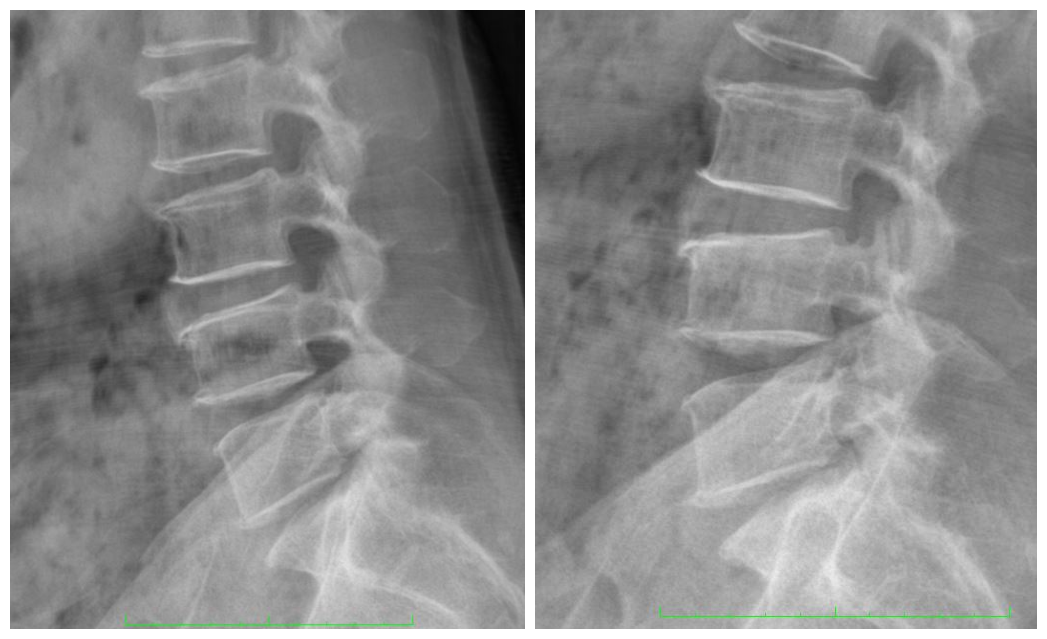

以下是我们查体资料展示:

我们治疗组将家属的顾虑和要求汇报于张宏主任,张宏主任详细阅片、细致查体后认同治疗组的治疗方案,耐心的向家属再次讲述了治疗方案和治疗的必要性。